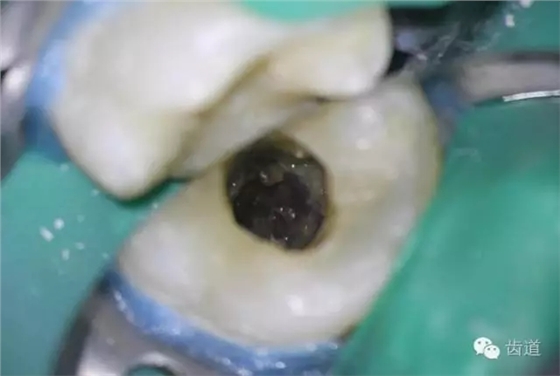

4. 初步開(kāi)髓

5. Endo-Z揭全髓室頂

6. 可見(jiàn)髓腔內(nèi)壞死牙髓組織,無(wú)滲出

7. 3%次氯酸鈉浸泡髓腔5min